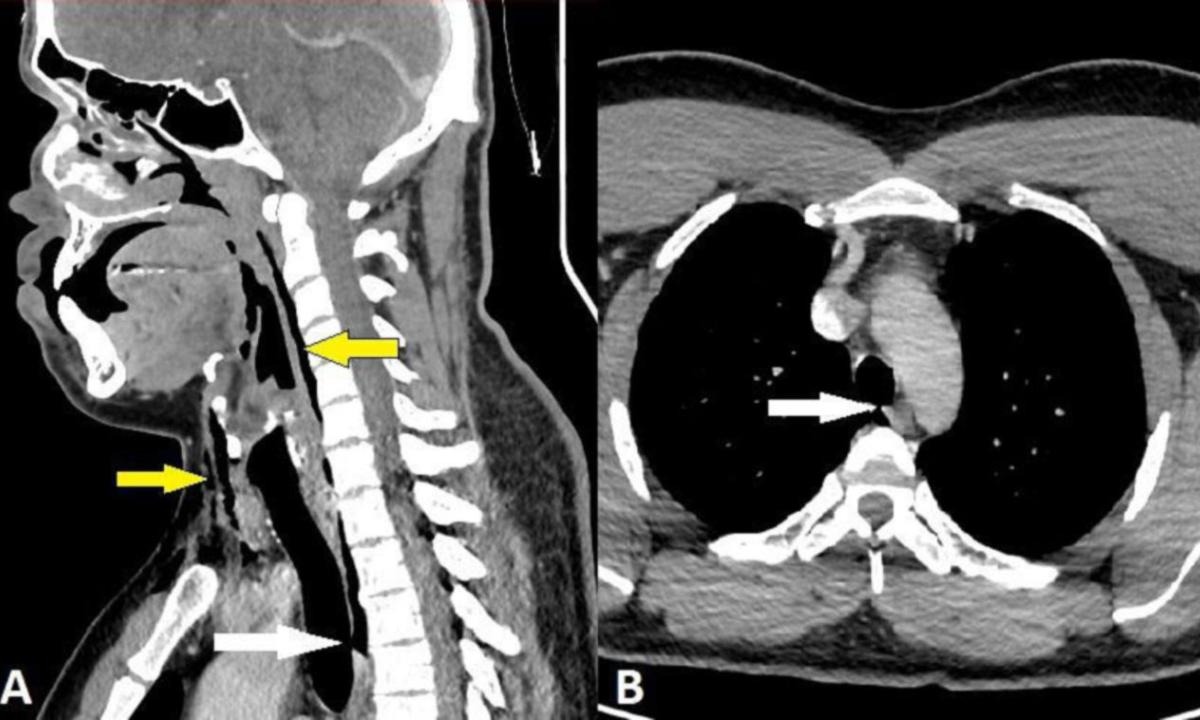

En las radiografías que le practicaron se confirmó que se trató de un enfisema quirúrgico.

En resumidas cuentas, el aire quedó atrapado debajo de las capas de tejido más profundas de la piel, ocasionándole un desgarro entre el tercer y cuarto hueso de la vértebra del cuello.

En el caso del hombre, la presión fue tanta que le abrió un agujero de 2 por dos milímetros en la tráquea.